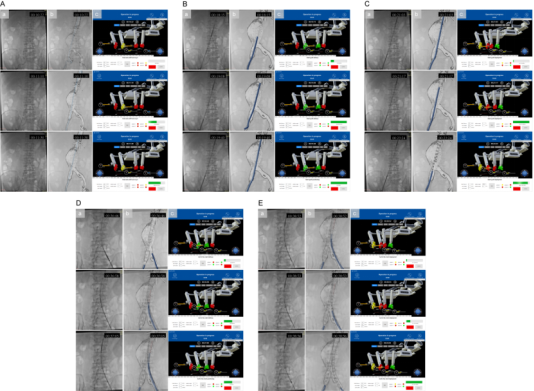

作为国家“新一代人工智能”专项承担单位,奥朋医疗凭借近百项国内外核心专利技术储备,此次手术实现四大核心突破,树立行业新标杆: 01 全球首创 EVAR 全流程自动化 首次实现从导丝推进、导管输送到支架精准释放的全环节无人干预操作,彻底突破现有机器人“手控为主、半自动为辅”的技术局限,将血管介入手术的自动化程度提升至全新高度。 02 独创“手术步骤参数化”新范式: 基于奥朋医疗自主研发的 Endosize软件,通过术前 CTA影像3D重建与精准建模,将复杂EVAR手术拆解为可编程、可重复的标准单元,自动生成器械运动参数,推动血管介入治疗从“经验依赖”向“标准量化”转型。 03 高兼容+多重安全保障体系: 系统兼容市售主流导丝、导管及支架等常规耗材,解决了传统机器人“耗材适配性差”的行业痛点;内置2N力反馈阈值自动暂停机制,搭配人机协同检查点、物理+虚拟双急停按钮,实现“精准操作+安全可控”的双重保障。 04 构建开放式智能介入平台: 该平台依托奥朋医疗“血管介入领域达芬奇”的技术定位,可无缝拓展至冠脉、神经、外周等8大介入领域,为未来融合AI自主导航、5G远程手术奠定坚实基础,彰显强大技术延展性。 图示:基于3D打印血管模型的体外验证实验。图中展示了支架植入的关键步骤,包括主体支架输送、精确定位、释放以及分支支架植入。本图包含三个视角:(A) 聚焦于血管模型的近景视图;(B) 展示整个实验环境的广角视图;(C) 操作台监视器界面的截图。 图示:自动化机器人辅助EVAR人体验证的支架植入过程。在导入超硬导丝后(见图4A),首先以10 mm/s的速度快速将支架输送系统推进至目标位置附近,随后以1 mm/s的慢速进行微调,最终实现支架在目标点的精准定位(见图4B)。随后进行支架释放,并通过逆时针旋转释放手柄5400°(转速90°/s)完成裸段释放过程(见图4C)。在人工完成对侧短腿超选并建立超硬导丝通道后,分支支架以与主体支架相同的方式输送并释放(见图4D、E)。 破解行业痛点,奥朋医疗给出中国方案 血管介入手术机器人虽已在临床展现出“提升精度、减少辐射”的显著优势,但长期面临两大瓶颈:一是难以兼容常规耗材,无法满足EVAR等复杂多器械协同手术需求;二是自动化局限于单一步骤,难以实现全流程闭环操作。而腹主动脉瘤作为“人体定时炸弹”,其主流治疗方式EVAR手术对操作精度、流程连贯性要求极高,传统人工手术不仅术者面临高辐射风险,还存在因经验差异导致的诊疗同质化难题。 在此背景下,奥朋医疗深耕“医工融合”创新理念,针对性研发全自动、高兼容、安全可控的主从式血管介入手术机器人平台,精准破解行业痛点,为复杂血管介入手术提供了兼具临床适配性与技术先进性的中国解决方案。 硬核技术支撑,临床数据彰显实力 该平台依托奥朋医疗“血管介入领域达芬奇”的技术定位,可无缝拓展至冠脉、神经、外周等8大介入领域,为未来融合AI自主导航、5G远程手术奠定坚实基础,彰显强大技术延展性。 本次研究采用奥朋医疗自主研发的主从式机器人平台,集成多自由度机械臂与高精度驱动模块,通过“术前精准规划—术中自动执行—阶段协同确认”的闭环流程,实现毫米级操作精度。研究先经3D打印血管模型充分验证,再成功应用于4例肾下型腹主动脉瘤患者,取得卓越临床成果: • 手术成功率100%:4例患者均顺利完成全流程自动化手术,术后CTA证实支架定位精准,无内漏及相关并发症; • 诊疗效率大幅提升:平均手术时间仅110分钟,透视时间19分钟,较传统手术显著缩短; • 辐射防护成效显著:术者辐射剂量低至4mGy,较传统手术减少90%以上,从根本上保障医护人员职业健康; • 稳定性全面验证:所有自动化步骤均未发生意外中断,无需人工接管,充分证明系统的临床可靠性。 (图示:血管介入手术机器人的组成与工作原理。(A) 血管介入手术机器人整体示意图。手术过程中,术者坐于操作台前(位于铅屏后方),远程控制从端机械单元;(B) 操作台的显示界面与功能说明;(C) 自动化机器人辅助EVAR手术的执行流程图。) (图示:基于Endosize软件的EVAR术前规划。图中展示了中心线及关键定位点。导丝的移动距离为从Pl点至P1点;导管的移动距离为从Pr点至P2点;主体支架的移动距离为从Pr点至P3a点;分支支架的移动距离为从Pl点至P4a点。) 引领行业变革,绘就智能介入新蓝图 作为当前全球唯一实现冠脉、外周、主动脉介入手术同步临床推进的企业,奥朋医疗此次突破性成果,不仅验证了全自动化EVAR手术的临床可行性,更通过标准化范式构建,为缩小不同层级医疗机构技术差距、提升基层诊疗同质化水平提供了有效路径。 未来,奥朋医疗将持续深化“精准、智能、微创”的技术理念,进一步拓展该平台至复杂主动脉病变、神经血管介入等更多场景,并融合AI实时导航、5G远程手术等前沿技术,推动血管介入手术向“自主决策、全域覆盖、优质资源下沉”的更高阶段迈进。正如奥朋医疗的发展愿景——致力于成为“血管介入领域的达芬奇”,以中国智造打破国际技术垄断,为全球患者带来更安全、更高效、更可及的医疗服务。